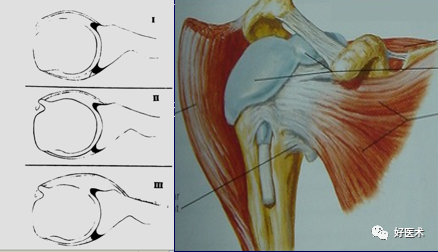

BLC 有三种类型:

-

Ⅰ型:BLC 牢固的与关节盂上极相连。

Ⅱ型:BLC 附着点在关节盂缘矢状面的内侧几毫米处。

Ⅲ型:盂唇在形态上与半月板相似。

(4)肱二头肌长头腱

肱二头肌长头腱起于盂上结节,并在附着处远端与上盂唇紧密相连,两者的胶原纤维相互编织构成肱二头肌腱盂唇复合体(BLC) 。长头腱在关节内走行于结节间沟。